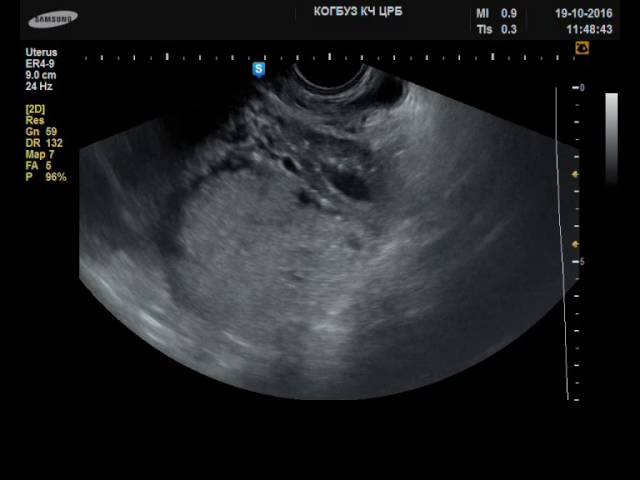

В ряде случаев выполняют лапароцентез: под контролем УЗИ устанавливают выводной канал, за одни сеанс выводится до 10 л жидкости. Состояние пациентки после этих процедур заметно улучшается. Но иногда возможны осложнения: появляются спайки, грыжа, значительно снижается давление и уровень альбумина в крови.